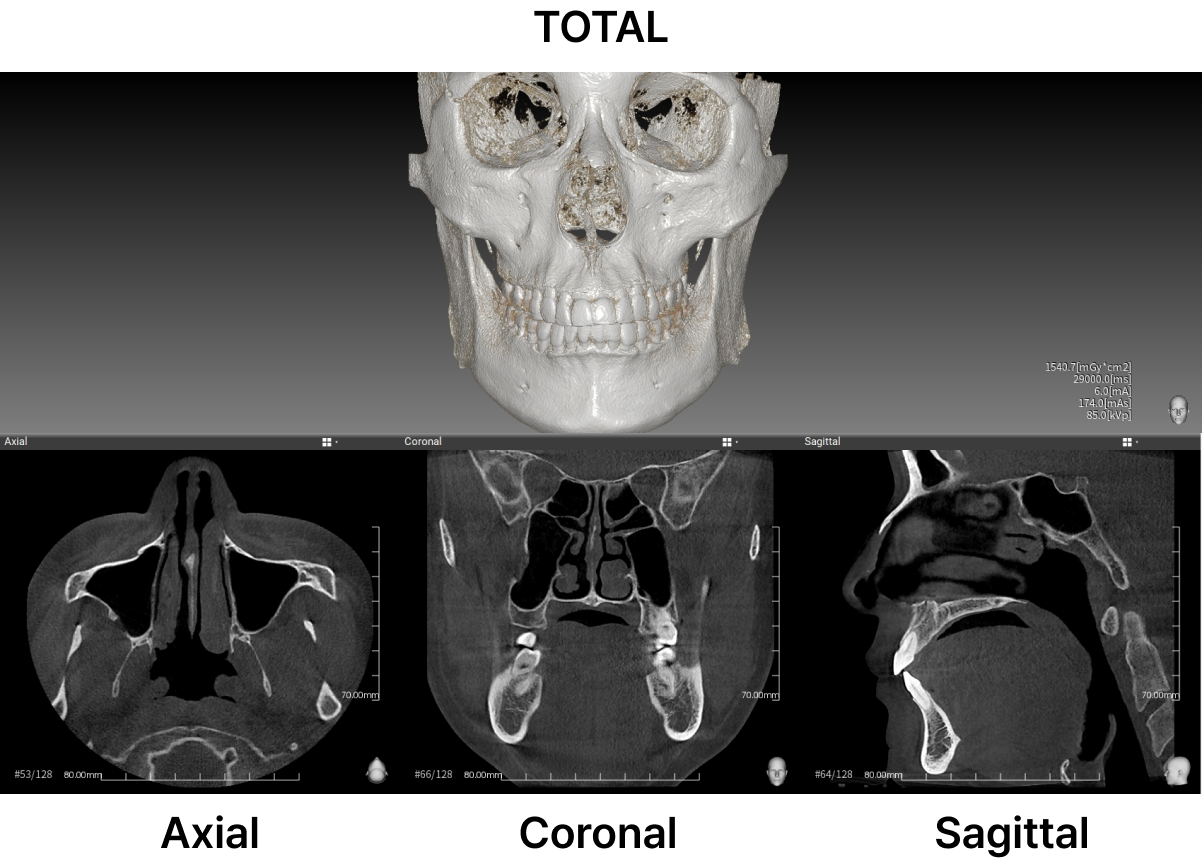

미용적인 부분 뿐만 아니라 코의 기능적인 부분까지 개선이 가능하며, 수술 전 3D-CT 장비를 활용하면 수술 부위의 뼈의 상태를 정확하게 파악 가능해 수술의 완성도를 높입니다.

아이뷰성형외과 퍼스널 3D-CT 코성형은 코의 외형적인 부분 뿐만 아니라 내부의 코 뼈의 모양, 휨, 비중격연골, 코막힘 등의 증상과 원인을 미리 파악할 수 있어,3D-CT를 이용한 입체적 분석으로 정확한 수술 계획을 수립하는데 도움이 됩니다. 혈관이나 신경 손상을 줄일 수 있어 안전하고 정확한 수술이 가능합니다.

코뼈와 비중격 연골 등 피부조직의 전반적인 상태는 육안으로 확인하기 어렵습니다. 3D-CT촬영을 이용하여 보다 정밀하게 분석이 필요합니다. 아이뷰성형외과 코성형은 3D-CT를 통해 보다 정밀하게 분석 후 1:1 맞춤 디자인 및 수술을 진행합니다.

아이뷰성형외과는 3D CT로 코의 골격구조, 코뼈의 넓이, 비대칭 유무, 매부리, 휘어짐, 비중격 연골 크기 등 면밀하게 분석하고 1:1 상담을 통해 개인의 요구조건을 반영하여 수술 계획을 세웁니다.